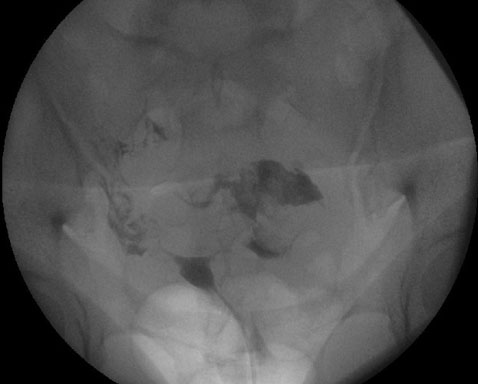

The patient was further scheduled for cystoscopy with bladder and urethral biopsies to assess the urethral mass seen on prior hysteroscopy. The gynecologic oncology team accompanied urology to attempt another hysteroscopy. With the patient’s history of cervical stenosis, the decision was made to attempt hysteroscopy using the flexible cystoscope. A 16 French flexible cystoscopy was used to first perform vaginoscopy and then easily traversed the cervical canal and allowed direct visualization of the endometrial cavity. Intrauterine survey revealed a large polypoid mass that was biopsied using a gastroenterology snare. Per chart review, the snare was able to collect an adequate sample and there were no long-term complications reported in subsequent gynecologic follow-up.

Exam under anesthesia revealed a vaginal introitus with a diameter of 1 cm that inhibited the insertion of a speculum or retractors. The cervix was palpated using one digit and found to be small and firm. A 5 mm hysteroscope was then introduced to visualize the cervix, but biopsy using an endometrial pipelle was unsuccessful. The 16 French flexible cystoscope was then used to perform vaginoscopy and successfully used to traverse the cervical os. The endometrial biopsy was again attempted using an endometrial pipelle with success. Samples were then sent to pathology. Per chart review, the samples obtained were adequate for diagnosis and there were no long-term complications reported in subsequent gynecologic follow-up.